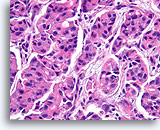

Invasief Ductaal carcinoom, Borst FNA, Celblok.

Met behulp van histologische coupes kunnen in sommige ductale carcinomen invasieve patronen geïdentificeerd worden [4]. Het invasieve patroon bestaat uit ductale cellen die binnen een actieve stroma groeien zonder lobulaire of ductale architectuur. De maligne cellen vertonen geen voorspelbare relatie met stromale referentiepunten en lijken het stroma onder willekeurige hoeken binnen te dringen. De kenmerken van invasiviteit worden in de volgende afbeeldingen geïllustreerd.

Invasief Ductaal carcinoom, Borst FNA, Celblok.

Met behulp van histologische coupes kunnen in sommige ductale carcinomen invasieve patronen geïdentificeerd worden [4]. Het invasieve patroon bestaat uit ductale cellen die binnen een actieve stroma groeien zonder lobulaire of ductale architectuur. De maligne cellen vertonen geen voorspelbare relatie met stromale referentiepunten en lijken het stroma onder willekeurige hoeken binnen te dringen. De kenmerken van invasiviteit worden in de volgende afbeeldingen geïllustreerd.

Ductaal carcinoom, Borst FNA, Celblok.

Let op de onregelmatige contour van de solide, smalle strengen met infiltratieve cellen (pijlen).

Ductaal carcinoom, Borst FNA, Celblok.

Let op de onregelmatige contour van de solide, smalle strengen met infiltratieve cellen (pijlen).